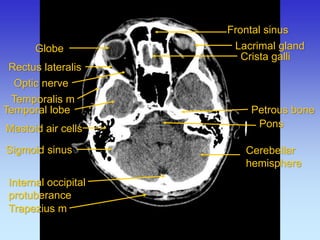

Frontal sinus

Lacrimal gland

Mastoid air cells

Petrous bone

Rectus lateralis

Crista galli

Temporal lobe

Cerebellar hemisphere

Trapezius m

Sigmoid sinus

Optic nerve

Pons

Temporalis m